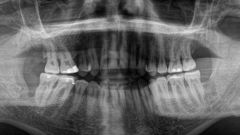

To provide Dental Health Care-Plan, please ensure you have the following available: Panoramic 2D X-ray less than 6 months old (see image example below)

Example 2D Panoramic X-Ray

2D X-Ray Panoramic View